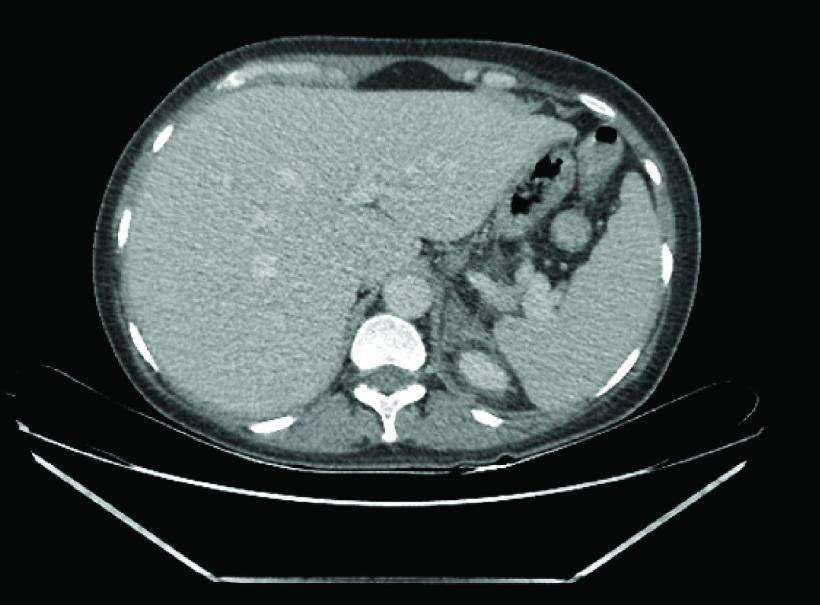

Abdominal pain is the most presenting complaint during pregnancy with multiple etiologies. The diagnosis could be unpredictable. We present a case of 36-year-old pregnant woman 10 7 2 at 36 + 5 weeks of gestation presenting twice for an increasing left abdominal pain, not relieved despite analgesics. She was delivered for severe oligohydramnios. After delivery, she was found to have a left adrenal infarction on computed tomography scan. She was found to have two mutations of the gene . Our presented case should remind physicians to consider the presence of thromboembolic state during pregnancy. The diagnosis of adrenal infarction should be among the differentials of an ambiguous flank pain that is resilient to medical therapy. Diagnosis in a pregnant patient can be easily confirmed with MRI, after which anticoagulation should be started and the workup for hypercoagulable state investigated.